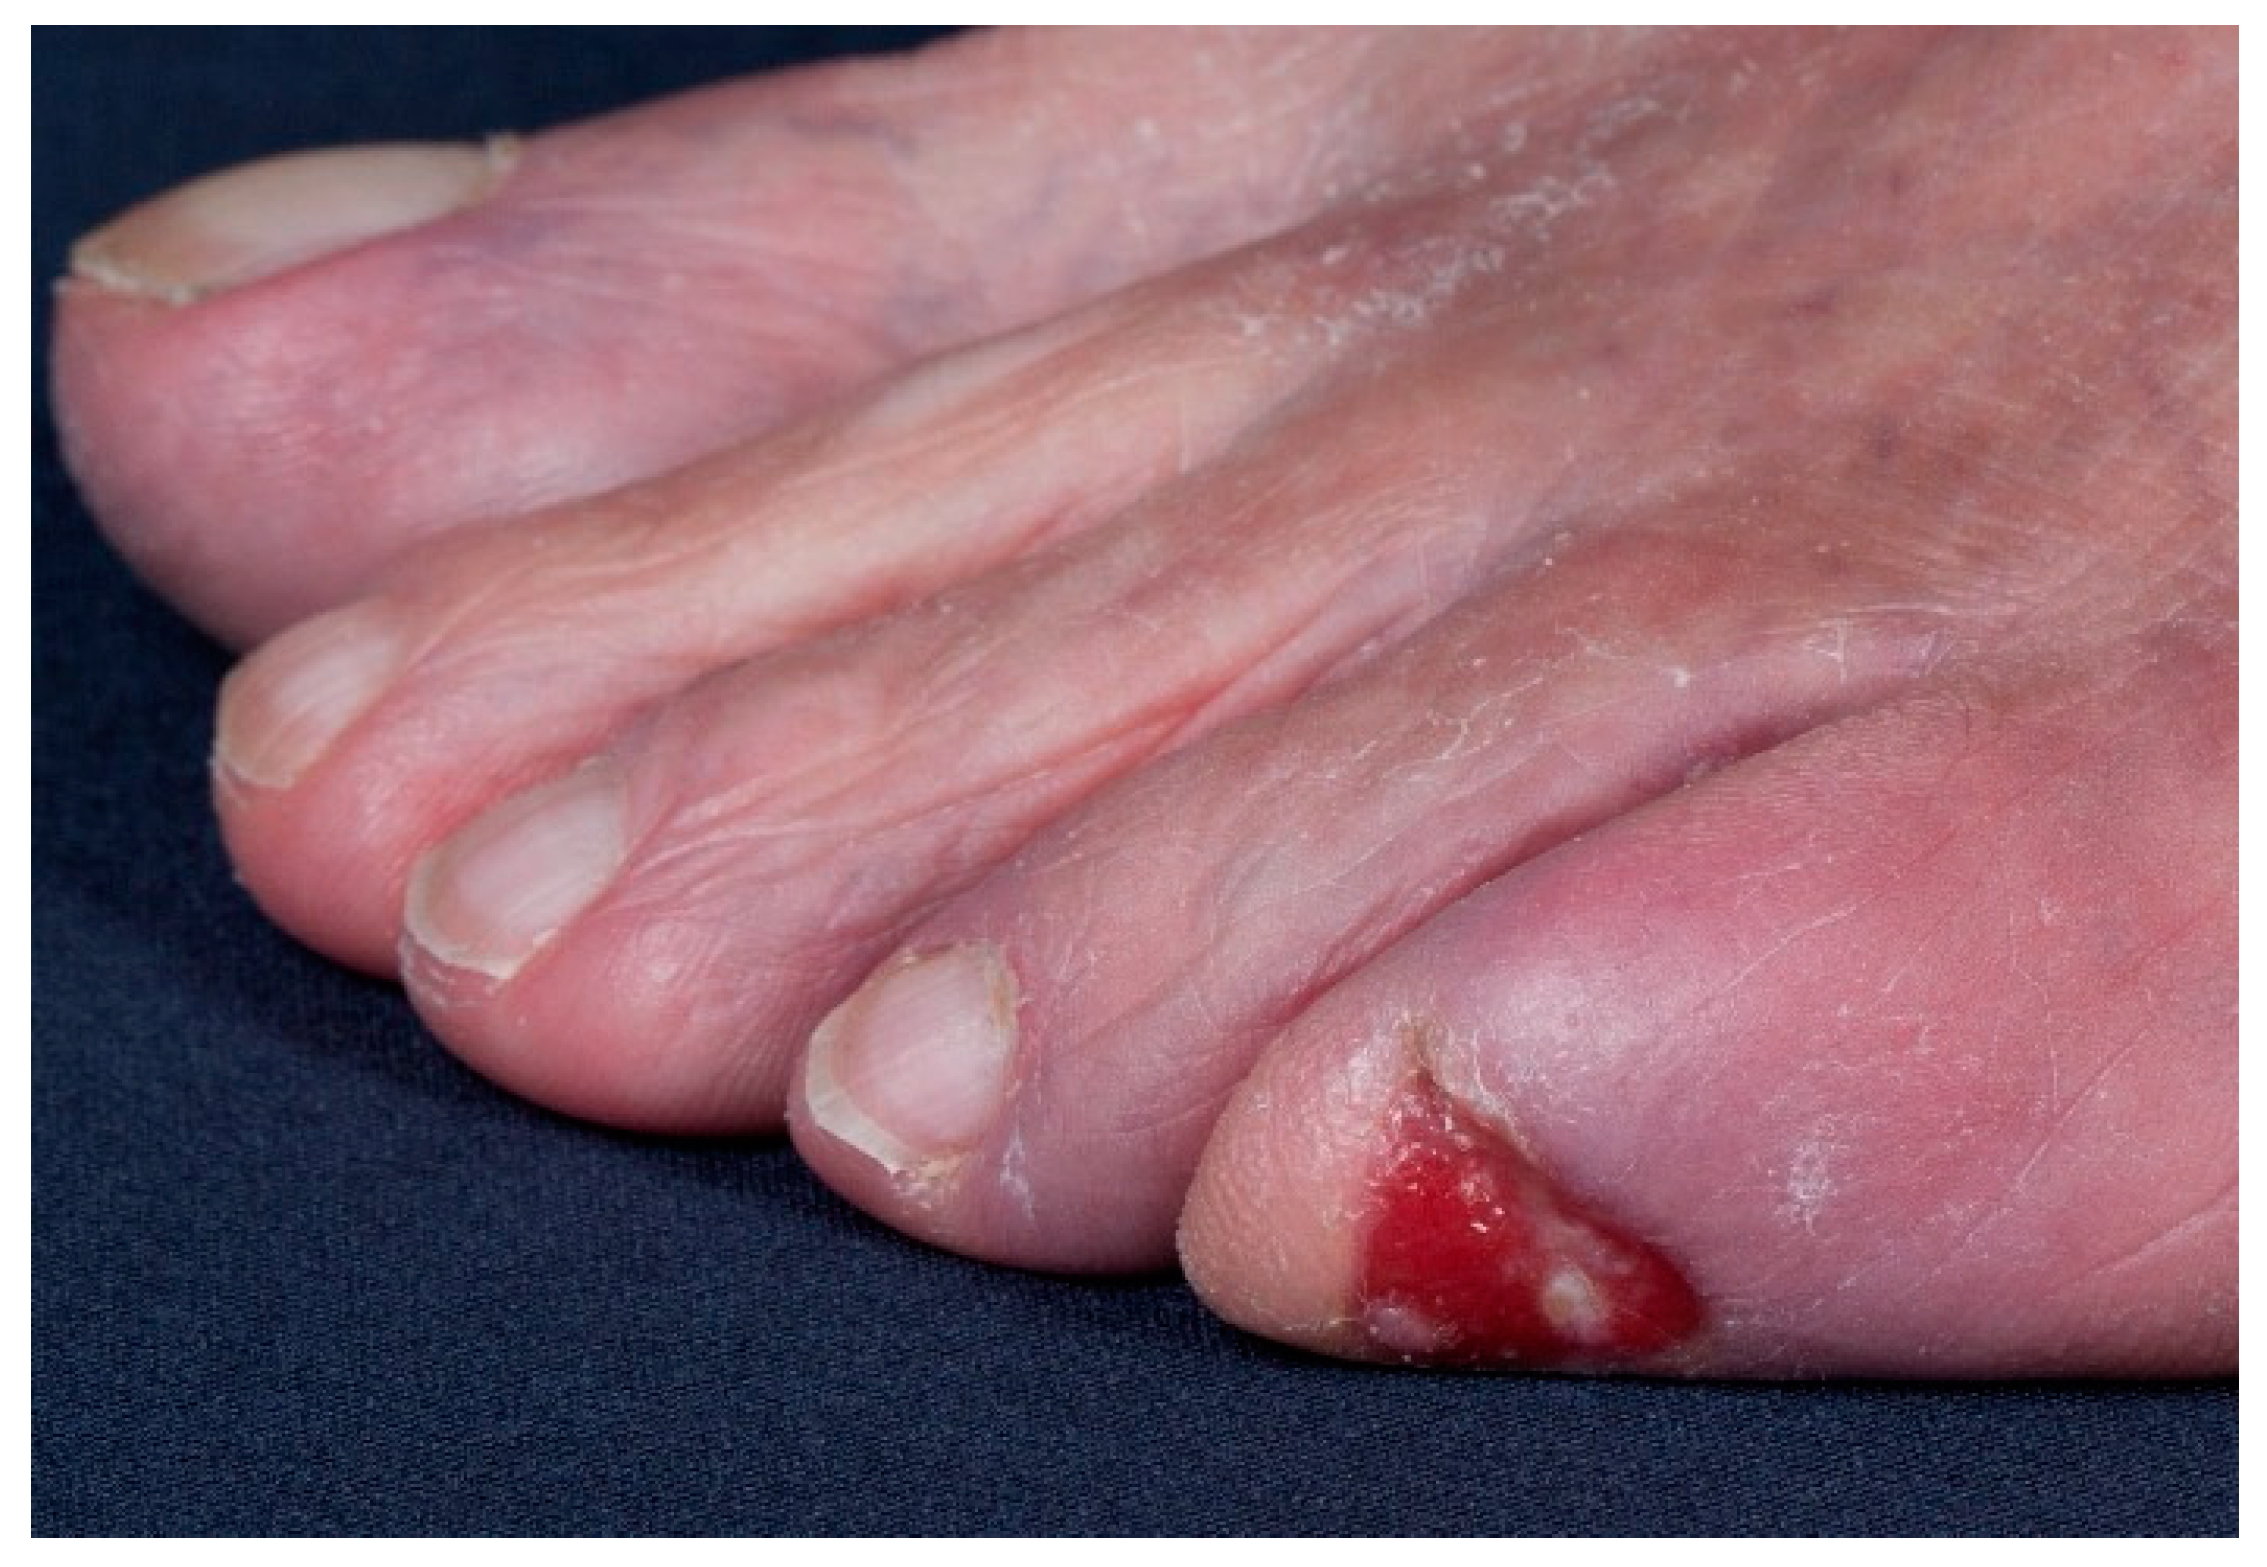

Malignant Tumours Presenting as Chronic Leg or Foot Ulcers